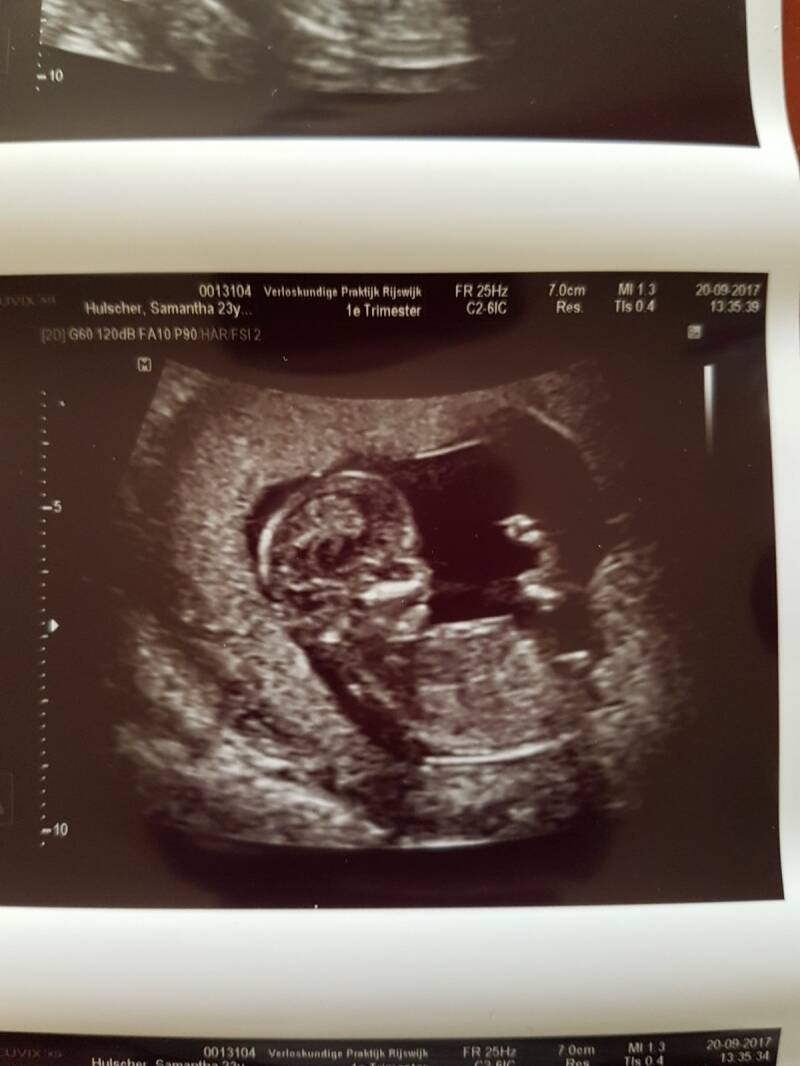

We gingen met een heerlijk gevoel slapen. Het gevoel Opa te worden is niet te vertellen. Je moet het worden om het te voelen. Mijn eerste ontmoeting met mijn kleinkind was een paar weken later via een echo foto. Prachtig om te zien en heerlijk om te horen dat alles erop en eraan zat. Nu lekker groeien tot aan mijn en jouw verjaardag.